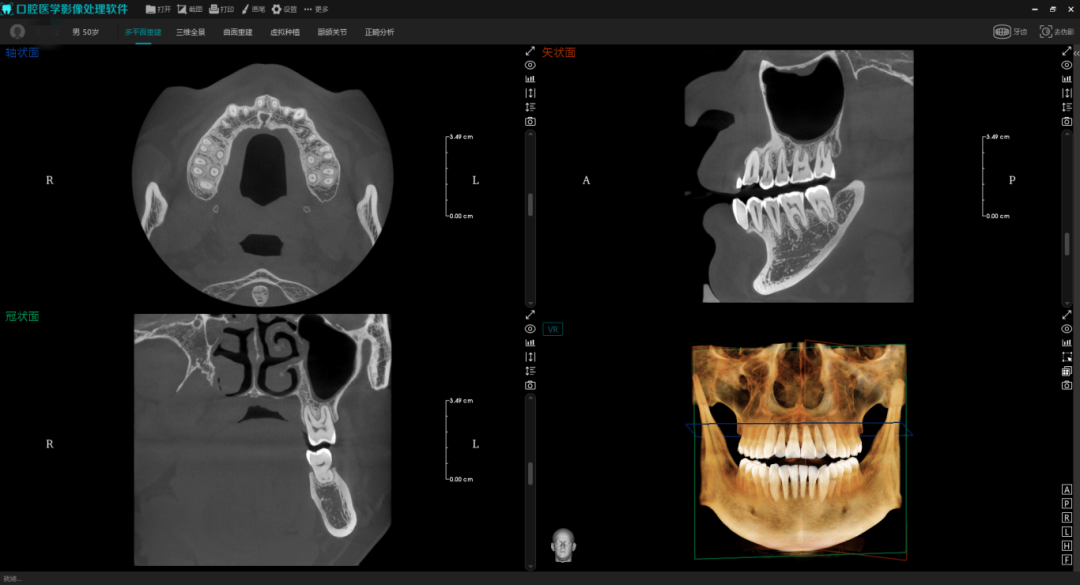

该标准首次在国家标准层面,为口腔颌面锥形束计算机体层摄影设备(以下简称“口腔CBCT”)建立了系统、科学的性能评价体系。其全面规范了口腔CBCT设备在验收和稳定性试验中的技术要求,聚焦影响诊断准确性与患者安全的关键技术指标,明确规定了空间分辨率、对比度噪声比、均匀性、几何精度、伪影评估等核心性能参数,同时对设备的辐射安全和图像质量提出了明确要求,助力实现从生产到应用的全流程标准化管理。

口腔CBCT影像

针对上述需求痛点,作为主要起草单位,美亚光电将深耕医疗影像领域十余年的技术积淀融入标准制定中。公司推出的新一代智能体CBCT,融合了AI、物联网与大模型等前沿技术,具备智能感知、智慧决策与自主进化能力,能有效应对影像采集、临床诊疗、设备运维等场景中的关键挑战。正是这些前沿技术成果,为国标条款的制定提供了重要参考,确保标准能够有效引领行业升级。